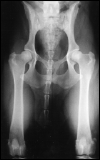

3. gestreckte Hüfte

Die Hintergliedmaße des Patienten sind gestreckt. PennHIP nutzt diese Aufnahme, um Anzeichen einer Arthrose im Sinne einer degenerativen Gelenkserkrankung zu identifizieren. Traditionelle HD-Untersuchungen werden oftmals nur in dieser Position durchgeführt. Bei einem klassischen Verfahren würde dieser Patient gut abschneiden, da in der gestreckten Aufnahme kein Hinweis auf eine Arthrose oder auch Lockerheit der Hüfte zu finden ist. In der 1. Distraktions Aufnahme hingegen sieht man, dass die Hüfte nicht den straffen Eindruck vermittelt, den sie in der 3. gestreckten Aufnahme zu erwecken versucht. Die Hüfte ist "locker". Somit steigt die Gefahr einer Hüftgelenksdysplasie, in vielen Studien nachgewiesen, deutlich an. Dieser Hund wird mit großer Wahrscheinlichkeit in seinem weiteren Leben eine Arthrose im Bereich des Hüftgelenkes entwickeln.